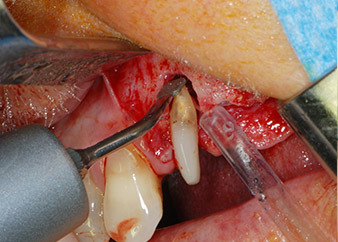

One month later, on the day of surgery, pain and inflammation at tooth 24 were minimal, but mobility of Miller class 2 was still present. After opening the flaps and cleaning the periapical and peri radicular infected tissue, the extent of the bone defect became obvious (Figs. 2 and 3).

total loss of bone and attachment

Fig. 2 and 3: After raising flaps, one month after endodontic revision and initiation of full-mouth periodontal therapy, the buccal root of tooth 24 showed a total loss of bone and attachment.

However, we maintained our initial plan to retain both teeth as temporary bridge abutments during the six-months osseointegration period of the implants. At reentry, the situation would have to be reassessed. First, in an attempt to manage the endo-perio problem, the remaining root surface was carefully debrided with piezoelectric equipment (Piezomed, W&H, used with the spatula-shaped insert S1, originally designed for erosion of the lateral sinus wall) (Fig. 4).